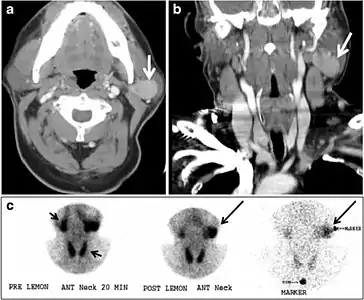

A thyroglossal duct cyst (TDC) is a duct remnant between the foramen cecum and thyroid isthmus. Most TDCs are located below the hyoid bone and in the midline. The more caudal the cyst, the more likely it will be off midline within 2 cm (Fig. 19 and and20).20). On a CT scan, a TDC appears as a well-circumscribed area of fluid attenuation with thin walls. The cyst wall can become thick with an enhancing rim indicative of current or previous infection. These cysts maybe complicated by haemorrhage, infection, or malignancy. Therefore, their US and CT scan appearance may vary based on their content. Nodular enhancement within a TDC should initiate further workup to exclude malignancy (Fig. 21). US-guided FNA of these suspicious nodular areas is considered an appropriate next diagnostic step, taking into consideration the high rate of false negative results.[1]